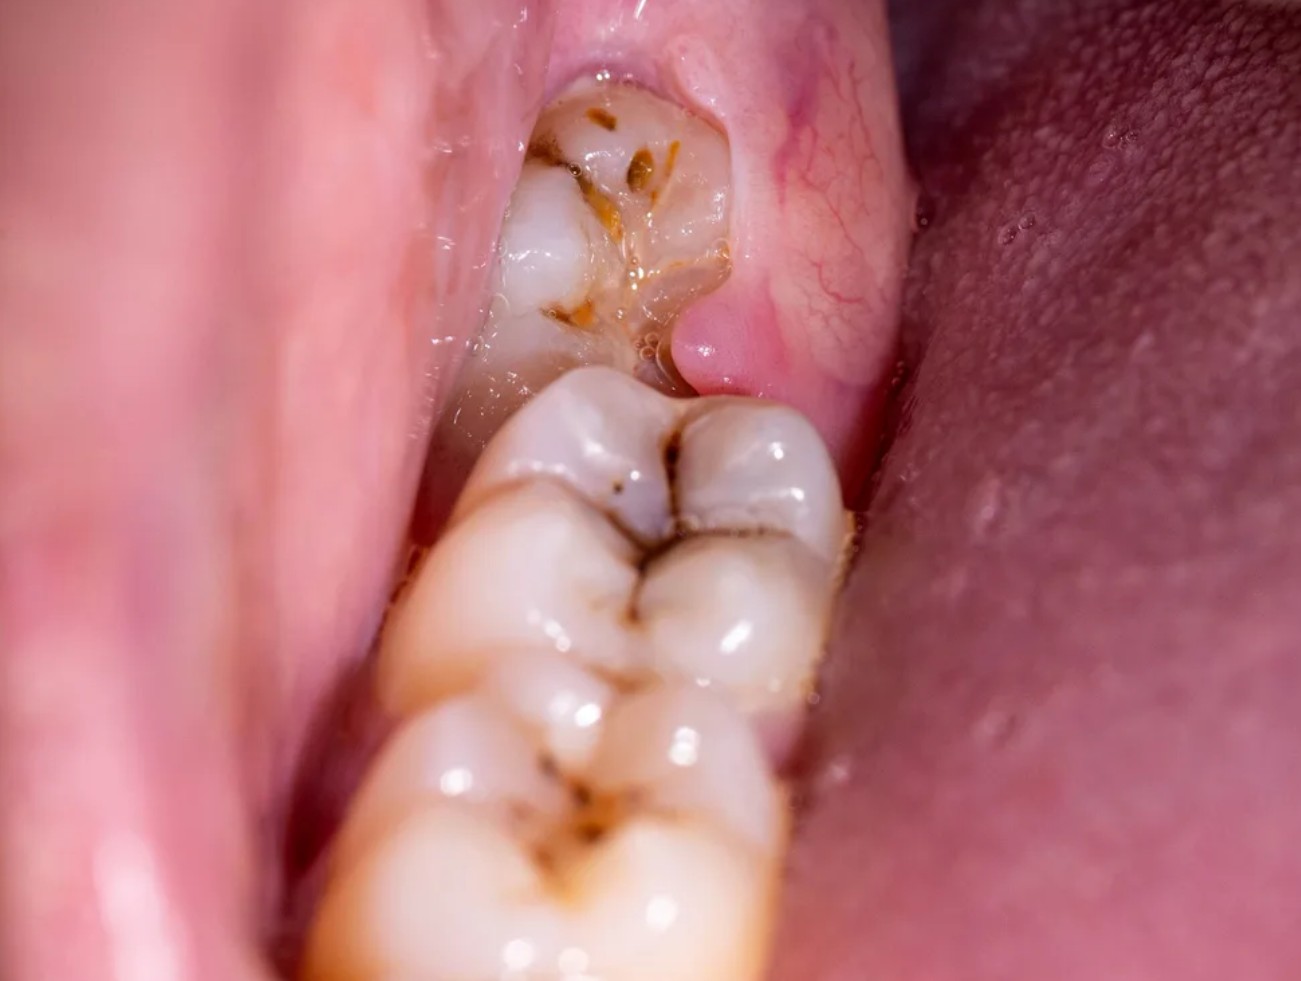

Khi răng khôn bắt đầu nhú khỏi nướu, đó là giai đoạn “chuyển mình” từ xương ra khoang miệng. Lúc này, một phần thân răng có thể đã xuất hiện, nhưng phần chân răng phía dưới vẫn còn đang hình thành và có khả năng tiến sát dây thần kinh hàm dưới. Chính vì vậy, việc đánh giá qua phim X-quang là vô cùng quan trọng để xác định hướng mọc và độ an toàn nếu cần nhổ bỏ.

Tuy nhiên, nếu răng mọc lệch, mọc ngầm hoặc bị kẹt dưới lợi, cơ thể sẽ phản ứng mạnh hơn. Những dấu hiệu cảnh báo cần đặc biệt chú ý gồm:

Nếu xuất hiện các triệu chứng này, đó là dấu hiệu răng khôn đang mọc sai hướng hoặc bị viêm quanh thân răng. Trong trường hợp này, việc trì hoãn thăm khám có thể khiến tình trạng viêm lan sâu hơn và gây biến chứng.

- Viêm lợi trùm tái phát, gây sưng đau và nhiễm trùng lan rộng vùng hàm mặt.

- Sâu răng số 7 do răng khôn đâm sát vào, tạo kẽ thức ăn khó làm sạch.